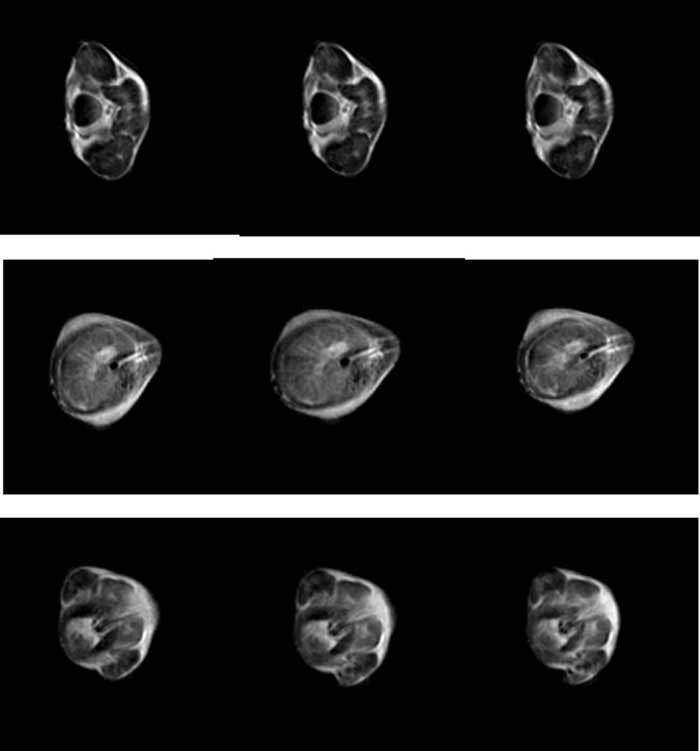

小鼠全身成像实验图片